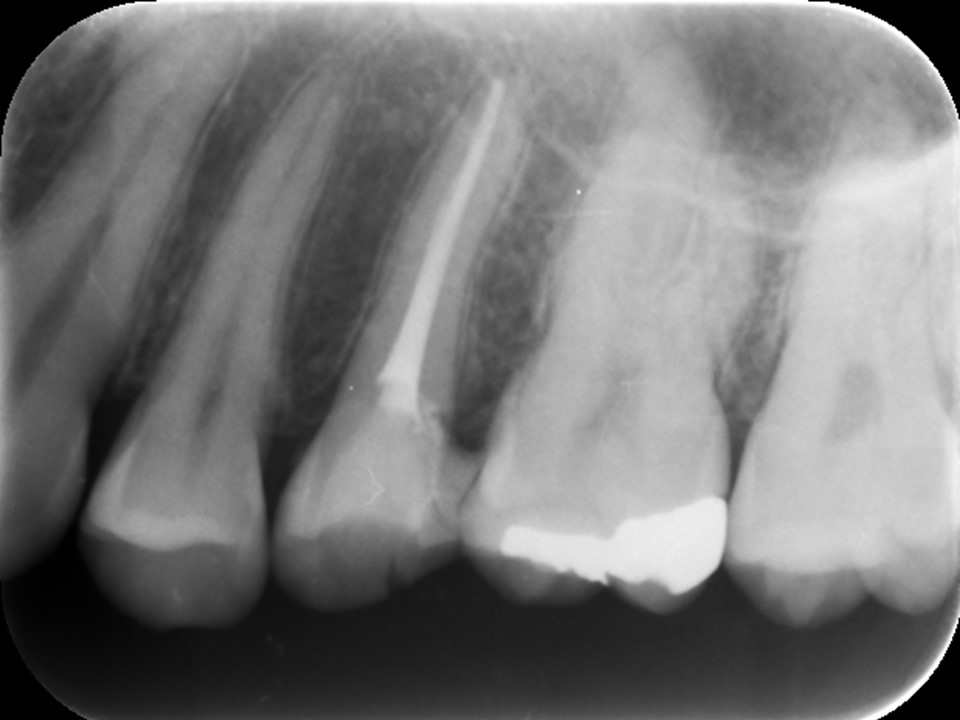

根管充填

マイクロスコープで根管内部がきれいになっているかを確認し、術前にあった症状が消失したら、ペースト状のバイオセラミックシーラーとゴム状のガッタパーチャで歯根の先端まで緊密に根管充填を行っていきます。

根管充填後レントゲン画像です。お薬が歯根の先端までしっかりと充填されているのが分かります。抜髄の場合、根尖部に細菌感染が及んでいないため、感染根管治療や再根管治療に比べて少ない治療回数で済むことが多いです。